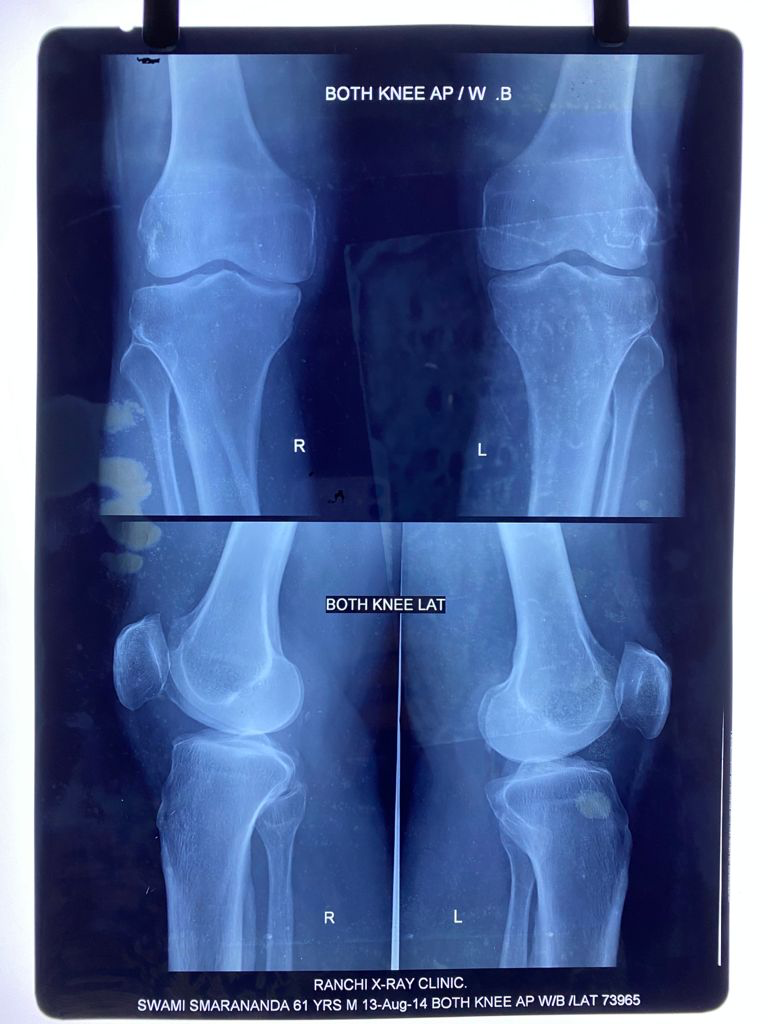

I had an episode of acute knee pain in June 2013. After studying the

X-rays and clinical examination, an Orthopaedic surgeon confirmed the onset

of osteoarthritis. He advised me to avoid climbing stairs and sitting

cross-legged. The doctor also forewarned me that I would have to undergo

knee replacement in 10 years.

August 13, 2014

August 14, 2014